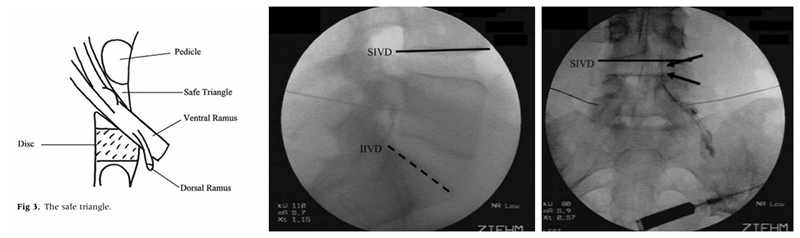

既然我们只需要把药物注射至神经根的周围而没必要注射至神经根鞘膜内,那么有没有一个更安全固定的穿刺点可以选择呢?答案是肯定的。Bogduk等提出了一种新的注射方法,该方法是将穿刺靶点设定在神经根的肩上,椎弓根的下方,Bogduk将这种方法称之为Sub-pedicular(SP)入路。穿刺的靶点称为安全三角(safe triangle):即椎弓根的下缘水平线,椎间隙外侧的垂直线和出椎间孔神经根的外缘线。该穿刺靶点有明确的骨性结构作为标志,可在影像引导下进行,同时将穿刺针尖远离了神经根。因此,提出了MRI椎间盘退变分型的Pfirrmann教授也发文力挺该方法,他认为在影像引导下采用这种方法进行脊柱注射术,是安全和精确的(safe and accurate)。SP入路很快便得到了广泛的认可和推广,至今仍有部分疼痛科医师使用。

图5

对各种注射方法的研究在当时激起了人们很大的兴趣,也随之出现了各种不同的称呼:神经根浸润术(nerve root Infiltration)、选择性神经根阻滞术(selective nerve root blocks)、选择性硬膜外注射术(selective epidural injections)、经椎间孔神经根注射术(Transforaminal nerve root injection)等。2003年,ISS(International Spinal Intervention Society, 国际脊柱介入学会)根据SP入路的特点,建议使用 Transforaminal injection一词。